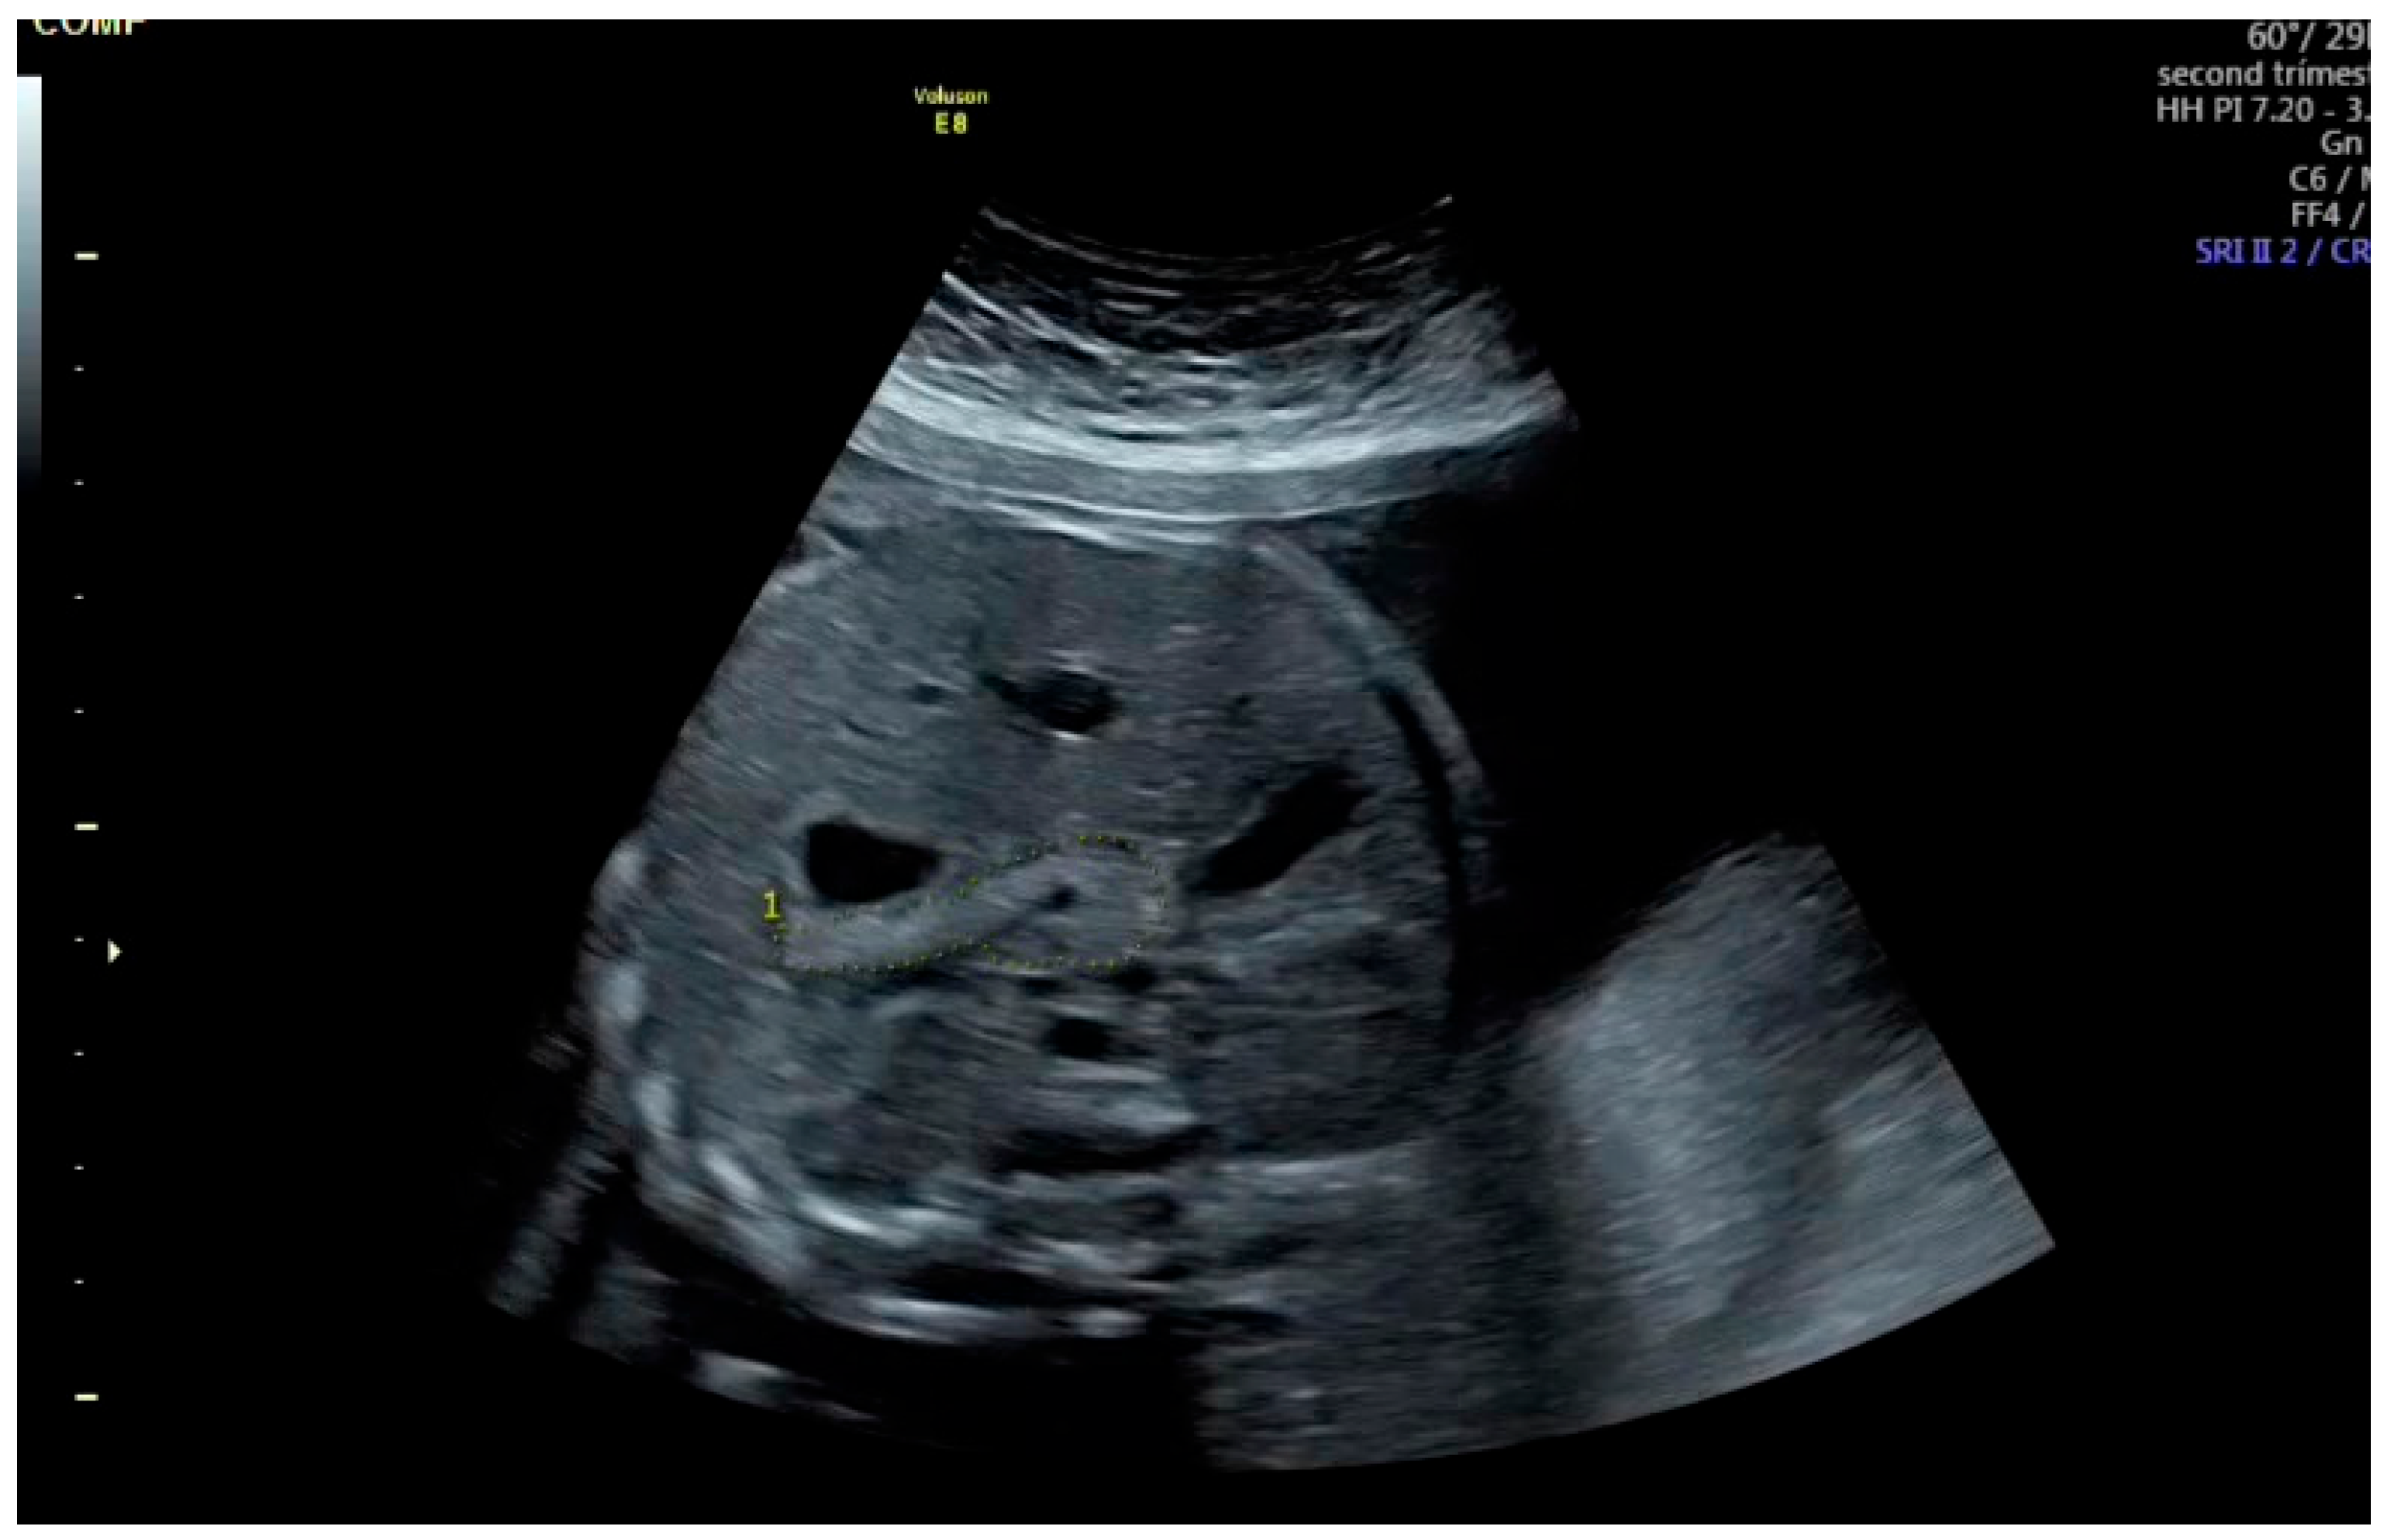

In our practice, the most suitable abdominal imaging plane was a transverse view at the level of the stomach and liver. However, as described by Güleroğlu et al., a slightly oblique plane with the fetal spine positioned between 3 and 5 o’clock or between 7 and 9 o’clock provided satisfactory visualization [13]. The stomach played a key role in identifying the pancreas; by tilting the transducer posterior to the stomach to locate the pancreatic tail, the entire pancreas appeared as a continuous longitudinal structure when the probe was rotated according to the fetal back position. The pancreas was visualized as a slightly echogenic structure located posterior to the stomach, anterior to the left kidney, aorta, superior vena cava, and vertebral column, extending toward the gallbladder on the right.

After freezing the image, the pancreatic circumference was measured using the freehand trace method (Figure 1). The measurement was repeated three times, and the mean value was recorded. Fetal pancreatic circumference percentiles were determined according to the reference data established by Kivilevitch et al. [7,14,15].

Figure 1. Gray scale ultrasound showing fetal pancreas circumference with dotted lines. The pancreas is seen as a slightly echogenic structure behind the stomach, anterior to the left kidney, aorta, vena cava superior and vertebral spine, and extending to the gallbladder on the right.